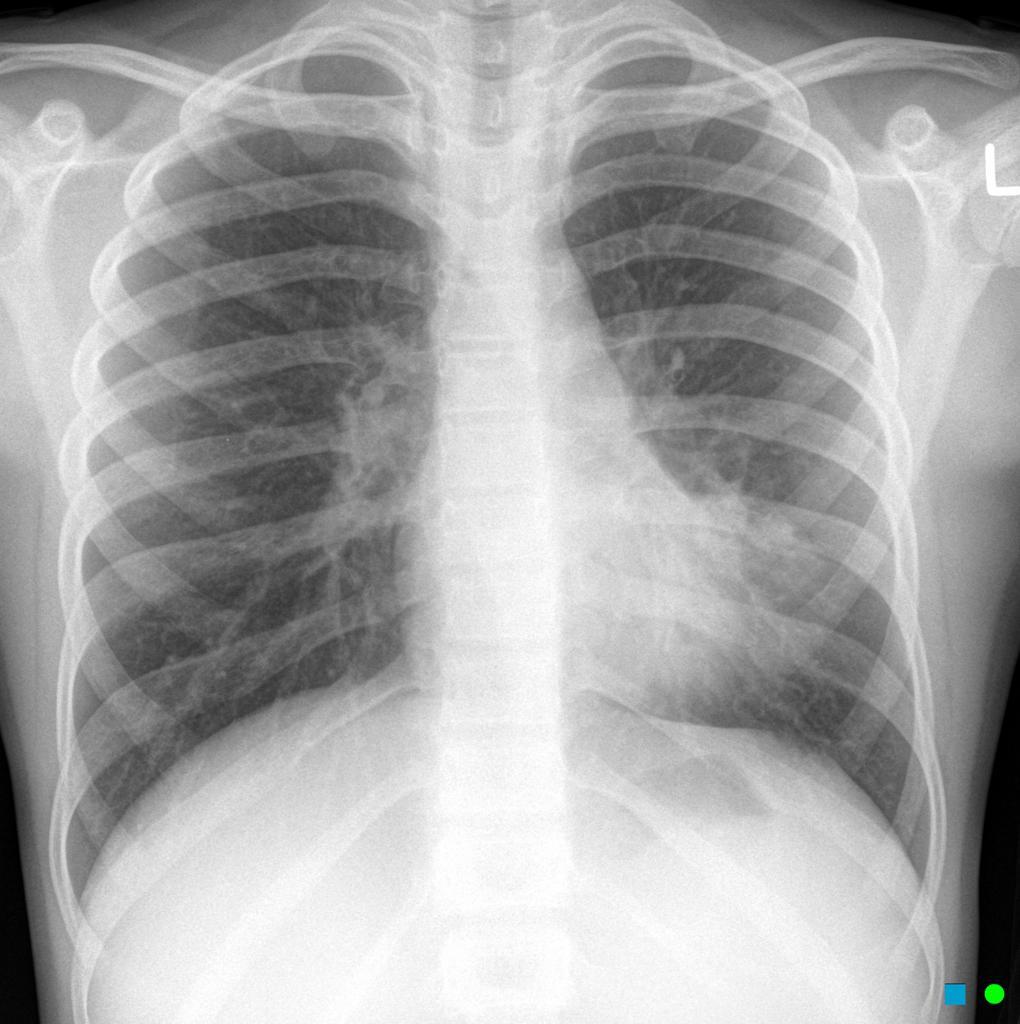

What does bilateral symmetrical hilar enlargement indicate?

Sarcoidosis

What does unilateral hilar enlargement indicate?

Malignancy

What does increased + absent lung markings indicate?

Increased = pathology (malignancy/ consolidation)

Absent = pneumothorax

What does loss of definition of right heart border indicate?

Right middle lobe consolidation

What does loss of definition of left heart border indicate?

Lingular consolidation